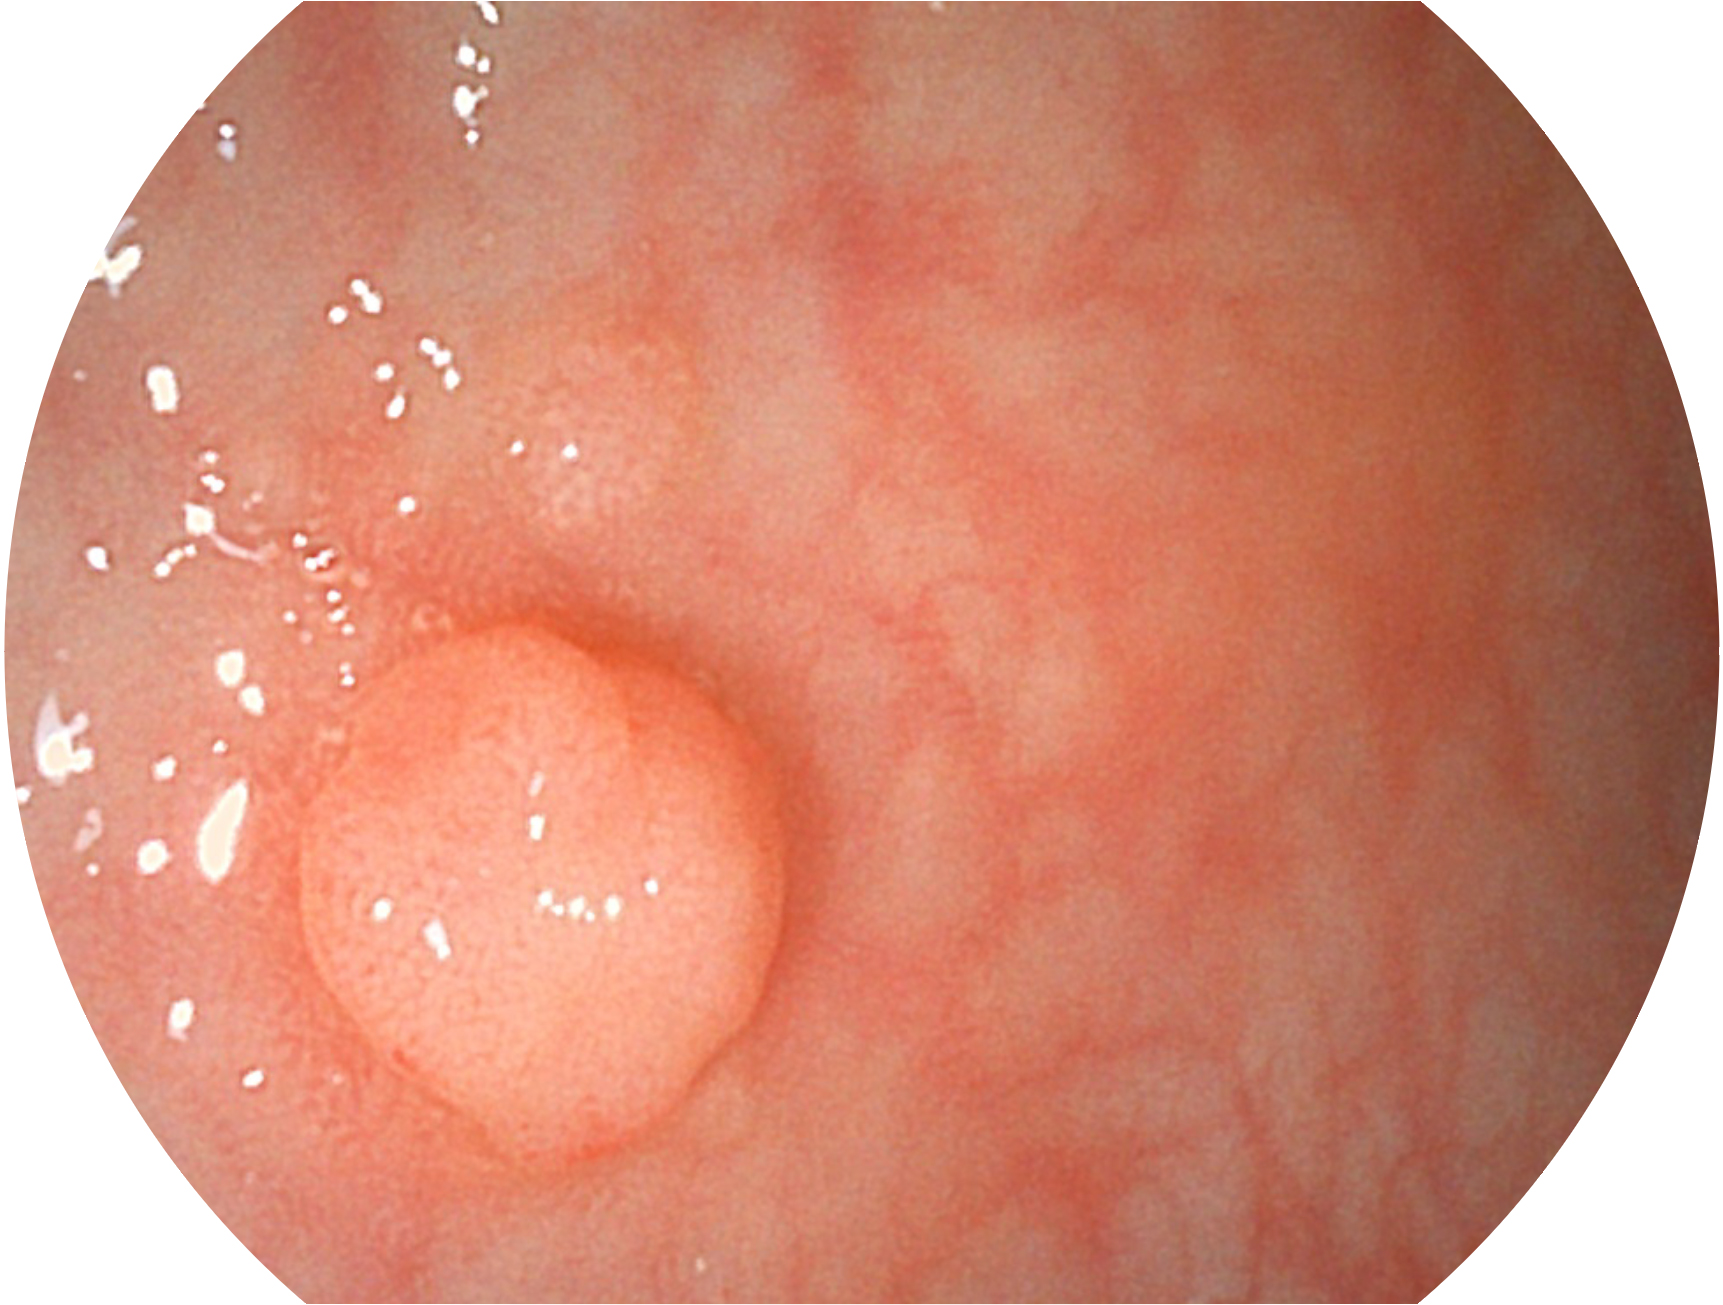

银河优越会新开发的内镜染色技术,主要是基于多波长LED 光源的开发,VLS-55Q 四波长LED 光源是由四个不同颜色的LED光按照相应照明模式所规定的特定发光比例进行合束后形成,合束后形成的照明光的光谱由红光、绿光、蓝光及蓝紫光这四个不同的波段范围构成。具有更高光谱自由度,通过光谱比例的控制,实现了聚谱成像技术,英文全称为“Spectral Focused Imaging, SFI”,缩写为“SFI”和光电复合染色成像技术,英文全称为“Versatile Intelligent Staining Technology, VIST”,缩写为“VIST”。